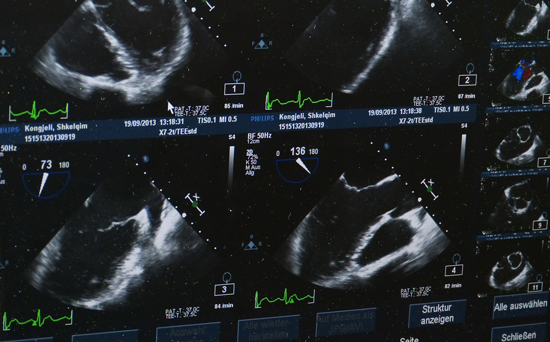

当卵泡成熟时,医生会安排取卵手术。医生会使用超声探头经阴道观测卵泡,使用取卵针刺破阴道壁进入卵巢,从卵泡中取出卵子,取卵的当天丈夫会同步进行取精。